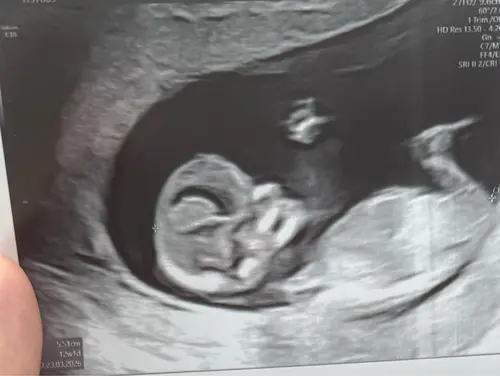

Oeh lastig, ik zie wel een nub maar vind het lastig om te zien of deze nu meer in een driehoek staat tov de ruggengraat of dat het recht door loopt 😅. Misschien zijn er kenners die het zien?

Weten jullie naar welke cirkel ik moet kijken? Dit is een 13,2 weken echo (tussen de beentjes) Bovenste lijken 2 streepjes van een meisje en daar onder lijkt een piemeltje.

Ik had bij mijn echo ook zo’n streep waardoor ik denk een jongen, maar als ik dan pottyshot foto’s zie van andere babies bij dezelfde termijn dan is het toch echt bij andere al beter te zien als het een jongen is.

Dus ik ben bang dat je nog een aantal weken moet wachten tot je zekerheid hebt 😅. Ga je een geslachtsbepalingsecho doen?